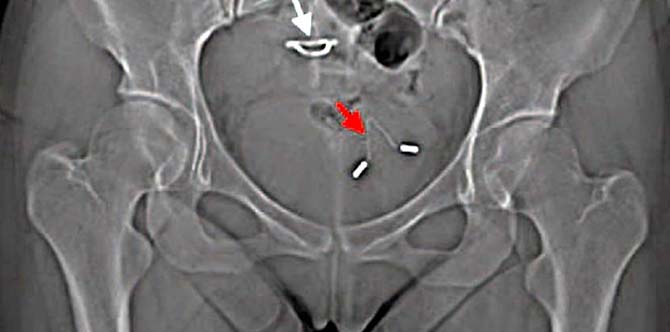

The red arrow in the X-ray shows the first IUD’s position in the woman’s bladder, while the white arrow shows the position of the second IUD | Image source: Medicine

A 26-year-old woman from China had been suffering from abdominal pain for the past five years. Doctors have finally identified the cause for her pain – an IUD that had been displaced and lodged in her bladder.

The X-ray revealed that the IUD had punctured her uterus and moved to her bladder.

What happened to her is an example of uterine perforation that happens to approximately one in every 1000 women who use an IUD, the Medical report stated. It isn’t common but it can and does happen.